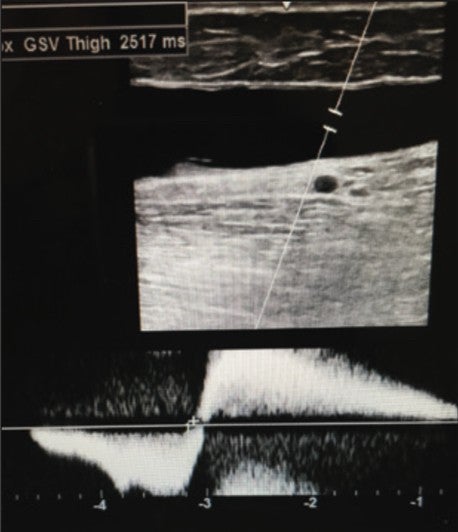

With ultrasound evaluation, patient exhibited significant superficial Great Saphenous Vein (GSV) reflux in his right leg as follows:

- Proximal GSV thigh: 2.5 seconds (Figure 1)

Figure 1. Pre-Varithena Treatment Rt. Prox. GSV Thigh: 2.5 seconds